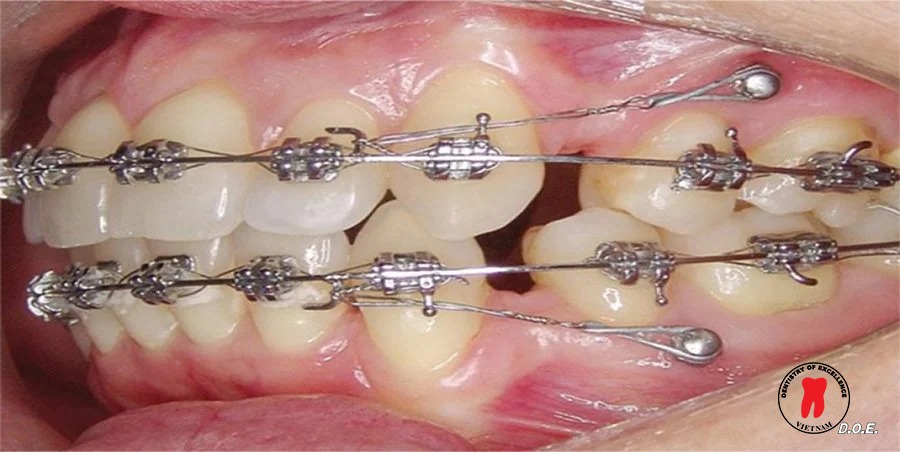

Minivis chỉnh nha là một loại vít titan kích thước nhỏ được đặt tạm thời vào xương hàm để tạo điểm neo chặn vững chắc trong quá trình chỉnh nha. Từ điểm neo này, bác sĩ có thể gắn các lực kéo từ dây cung, lò xo hoặc thun chỉnh nha để dịch chuyển răng theo hướng mong muốn.

Việc sử dụng minivis giúp bác sĩ kiểm soát tốt hơn cơ học chỉnh nha, đặc biệt trong các trường hợp cần dịch chuyển răng phức tạp như kéo lùi răng cửa, đóng khoảng sau nhổ răng hoặc chỉnh khớp cắn…

Thiết kế này cho phép gắn dây cung, lò xo, thun liên hàm hoặc các khí cụ chỉnh nha khác một cách linh hoạt. Nhờ vậy, minivis Dentos có thể được sử dụng trong nhiều cơ học chỉnh nha khác nhau, từ các ca điều trị đơn giản đến những trường hợp phức tạp.

Ngoài hiệu quả cơ học, yếu tố thẩm mỹ cũng được nhiều bệnh nhân quan tâm. Minivis Dentos có kích thước nhỏ và thiết kế gọn, giúp giảm cảm giác vướng víu trong khoang miệng.

Vị trí đặt vis thường nằm ở những khu vực ít lộ ra khi cười, vì vậy không ảnh hưởng nhiều đến thẩm mỹ trong quá trình điều trị chỉnh nha.